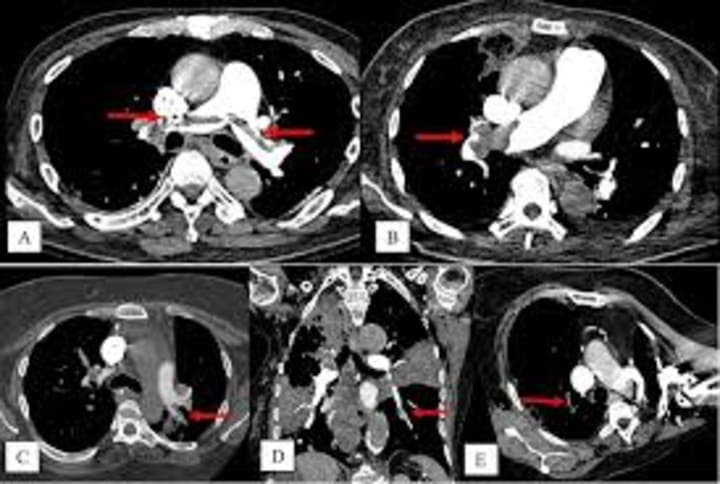

I work mostly within computed tomography so in cases of pulmonary embolism we will either do a plain Chest CT or usually a Chest CT with PE protocol, which uses contrast to enhance the veins.

The image above shows how the obstruction would appear within a CT Chest PE protocol image.